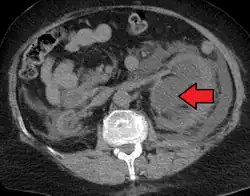

Massive hydronephrosis as marked by the arrow -